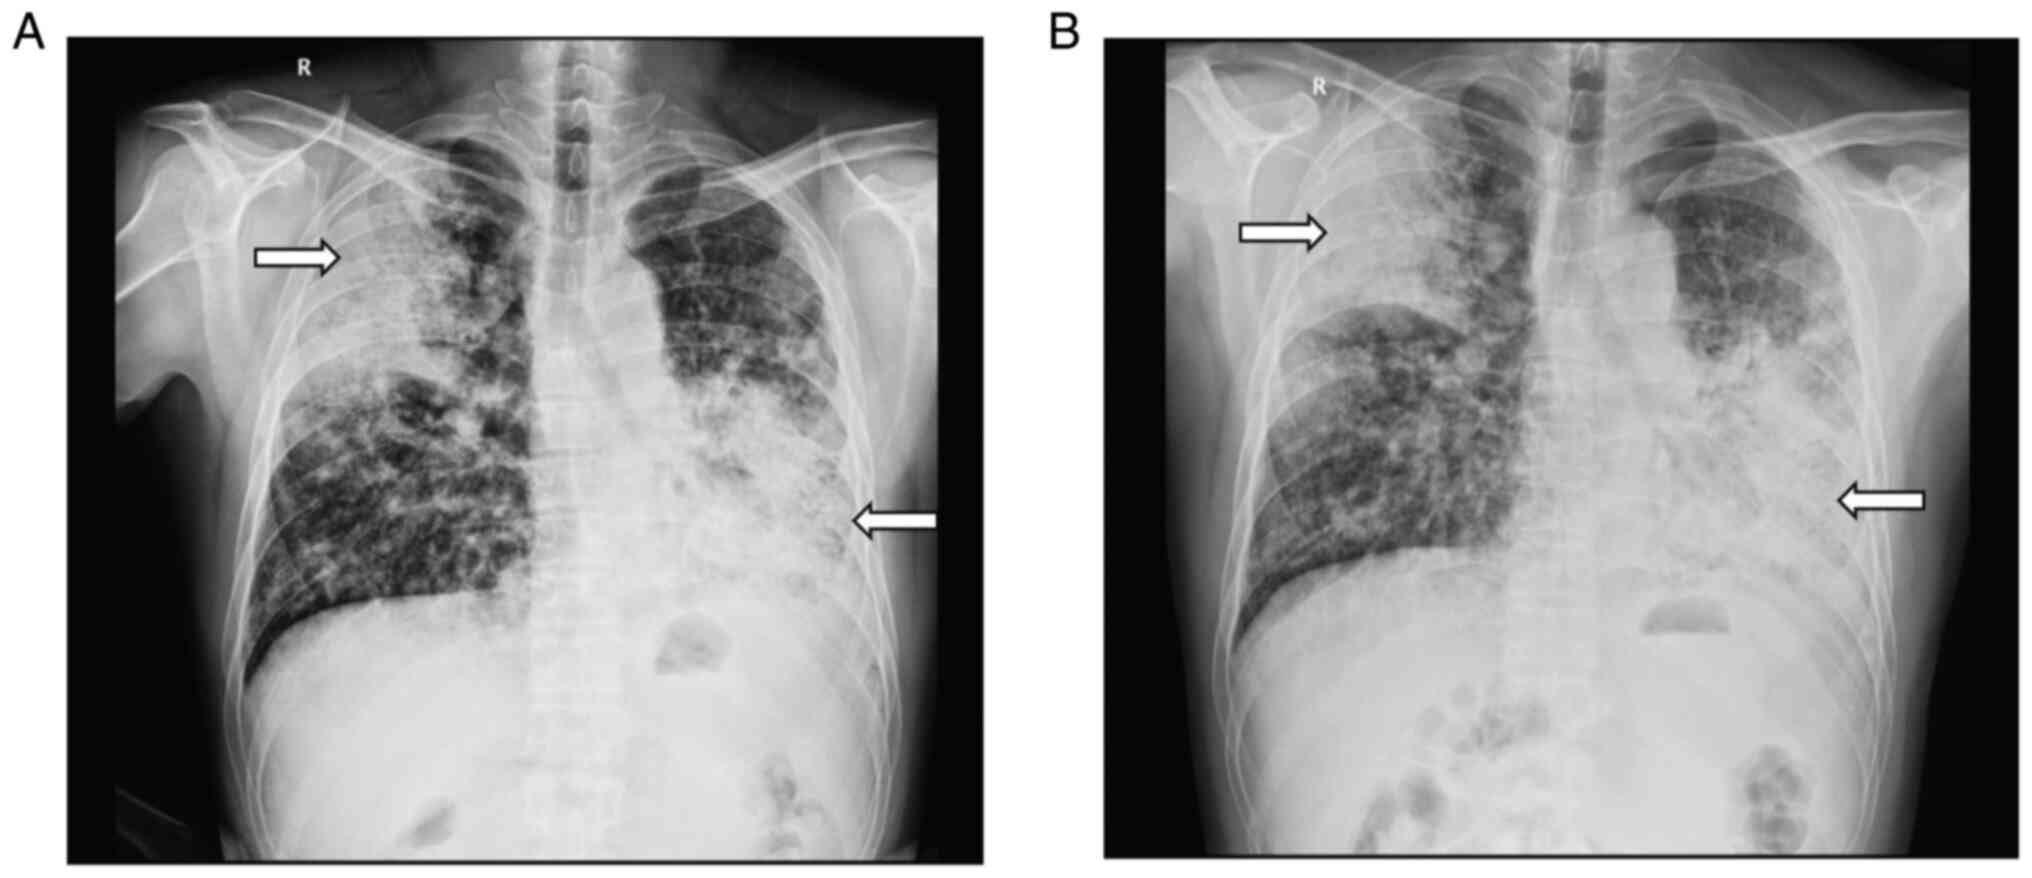

A 45-year-old male complained of a cough with production of sputum without obvious cause for a year. He denied chest pain, fever, chest tightness, shortness of breath, hemoptysis, night sweats, palpitations, eyelid edema and extremity edema. He was treated at another hospital and diagnosed with ‘pneumonia’. He was discharged from the hospital with symptom improvement after anti-infection treatment. Following discharge, he repeatedly coughed, with sputum production. For every episode, his symptoms were relieved after anti-infection treatment. However, the symptoms recurred and became worse after 2 days of treatment. Chest digital radiography (DR) showed diffuse, patchy and blurry density shadows throughout both lungs (Fig. 1A). He was transferred to the Departments of Pulmonary and Critical Care Medicine, The First Affiliated Hospital of Chengdu Medical College, for further treatment.

Figure 1

DR of the chest. (A) DR imaging before anti-infective treatment in The First Affiliated Hospital of Chengdu Medical College in March 4th, 2019. (B) DR of the Chest in The First Affiliated Hospital of Chengdu Medical College in March 22, 2019 after anti-infection treatment. Arrows indicates the patchy and flocculent fuzzy density shadows that are diffusely distributed in both lungs. DR, digital radiography.

The patient received empiric antimicrobial therapy following admission. Combined cefuroxime sodium (0.75 g/8 h, intravenous injection) and moxifloxacin hydrochloride (0.4 g/day, intravenous injection) were administered for anti-infection treatment. According to the results of chest CT and enhanced chest CT, it was possible to consider infectious lesion. At one week following anti-infective treatment, chest DR examination showed that the lesions were more advanced than before (Fig. 1B). The T-SPOT test was positive but with a small number of spots. The possibility of tuberculosis was low. The patient's tumor marker levels were significantly elevated. IMA could not be ruled out. Thus, fiberoptic bronchoscopy was performed and found no obvious morphological change (Fig. 3). The pathological examination suggested that the mucosal epithelium was undergoing chronic inflammatory changes with mucosal epithelial cell proliferation (data not shown). A case discussion in Departments of Pulmonary and Critical Care Medicine, The First Affiliated Hospital of Chengdu Medical College considered a tumor diagnosis according to the tumor marker and pathology results. A percutaneous lung puncture biopsy was performed (Fig. 4A). The collected samples were fixed in 10% neutral buffered formalin 24 h at room temperature and embedded in paraffin. Sections were cut at 5 µm and hematoxylin-eosin and thyroid transcription factor 1 (TTF-1) immunohistochemical (IHC) staining (6) were performed following the manufacturer's protocols. The adenocarcinoma was diagnosed based on the pathological staining which were evaluated independently by two pathologists at the First Affiliated Hospital of Chengdu Medical College in a double-blinded manner (Fig. 4B and C). Pathological specimens were almost negative for all driver genes, except KRAS (Table I). However, there was no KRAS G12C molecular targeted drug in 2019 and the patients and family refused treatment, including chemotherapy, radiotherapy and interventional chemotherapy and the patient was discharged from the hospital.